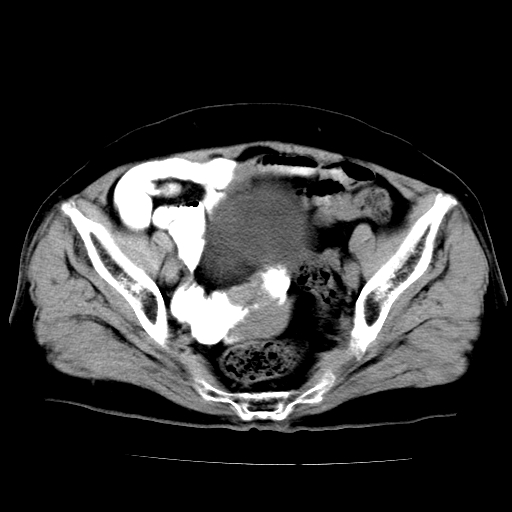

女,73岁,阴道流血一周。

宫颈不规则增大;结合临床考虑宫颈癌。建议作mri检查

1\\老年妇女突发阴道流血,常见病考虑宫颈癌.本病例宫颈部显示形态不规则,密度欠均匀,支持考虑宫 颈癌,建议mri 或阴道超声坚持

2\\但是盆腔两侧尚未见到明显肿大淋巴结等转移征象

宫颈不规则增大,左后方可见结节状突起.支持宫颈癌.

宫颈壁明显增厚,左侧为甚,宫颈癌待排,建议宫颈涂片细胞学检查。

宫颈不规则增大,周围脂肪间隙毛糙,结合临床考虑宫颈癌,盆腔内未见肿大淋巴结。